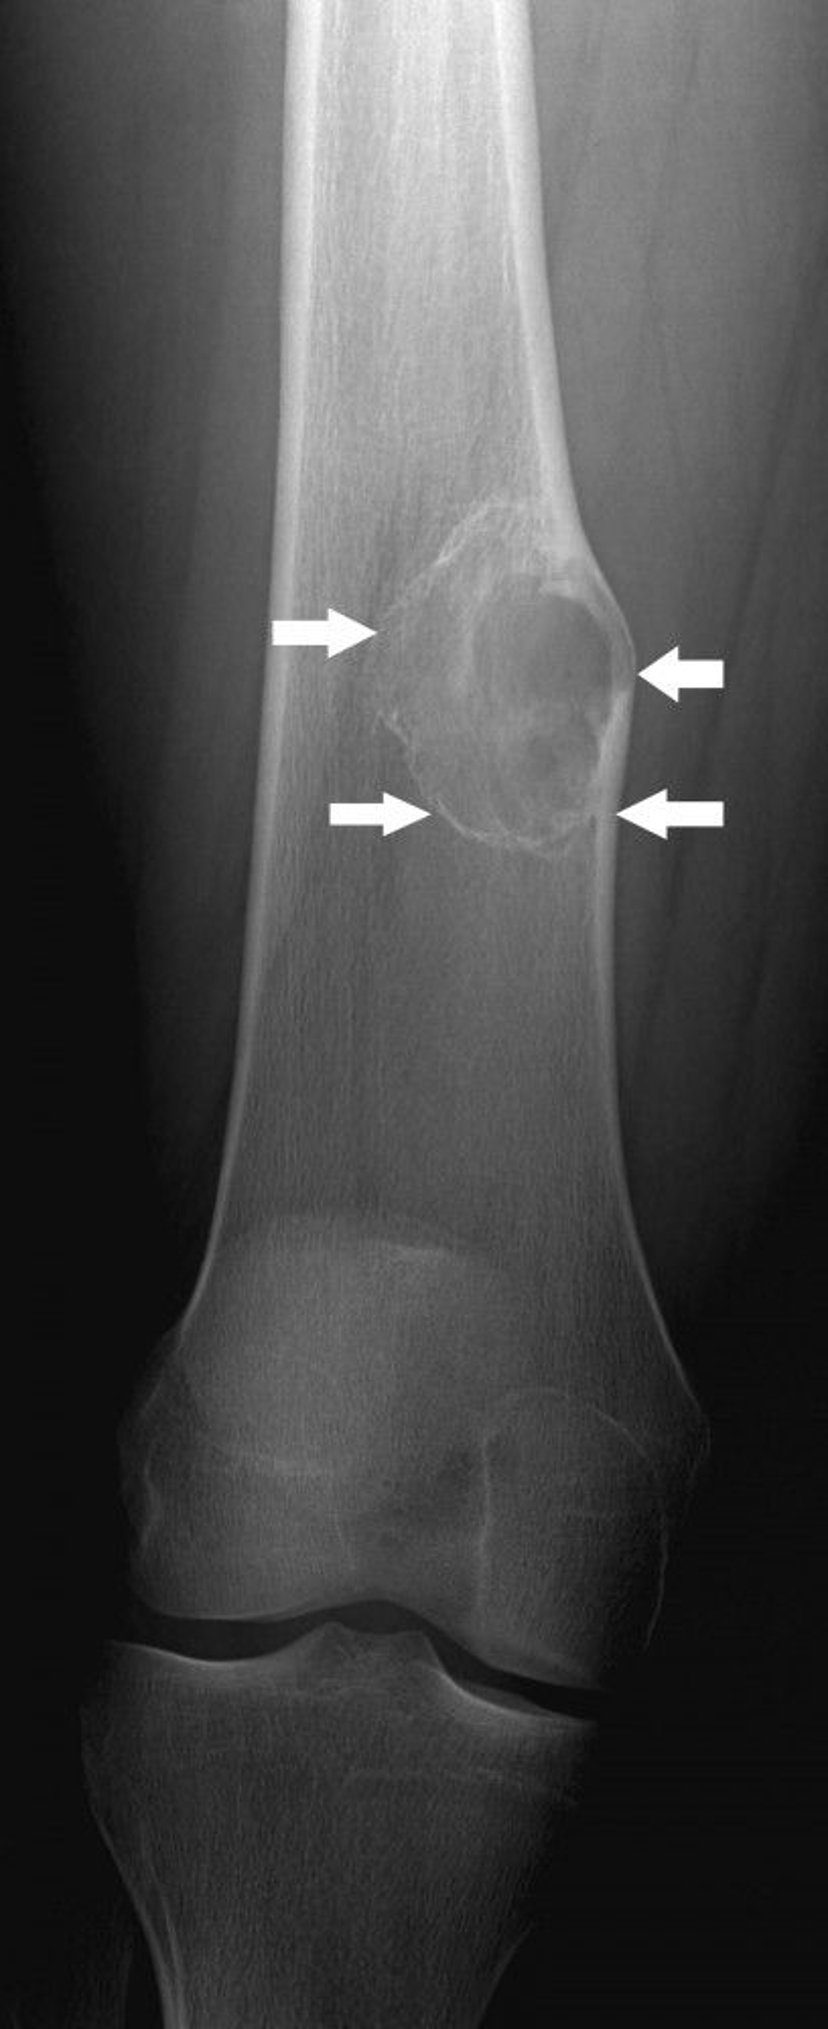

This x-ray shows a nonossifying fibroma (arrows) above the knee in the thigh bone.

Image courtesy of Michael J. Joyce, MD, and Hakan Ilaslan, MD.